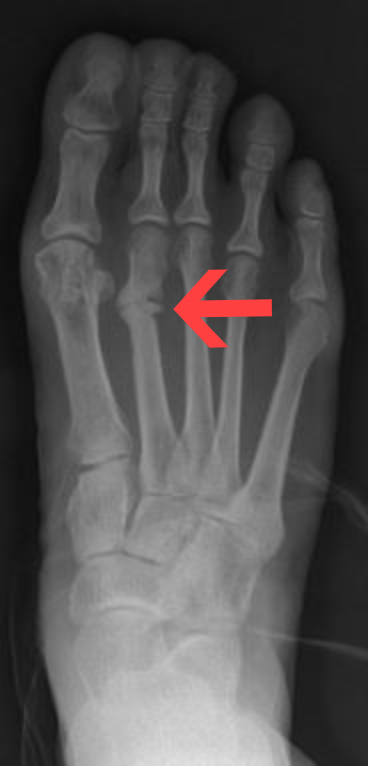

Fractures

are breaks or cracks in bones.

greenstick

Impacted

Closed

Open

Comminuted

Pott’s

Colles’

Stress